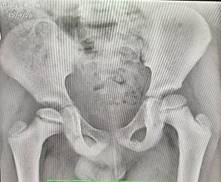

Se solicitó una radiografía de pelvis ósea en cuerpo de guardia en vista anteroposterior (Ver Fig.1) y en vista de rana (Ver Fig.2), donde se muestra una alteración del contorno superior de la cabeza femoral derecha, y se observó una imagen lineal que corresponde a una fractura subcondral. Además, se percibió el signo de la media luna de Waldestrom. Esto coincide con la etapa fragmentación, es clasificada así según los criterios de Herring en Grupo B, ya que existen cambios en la altura del pilar lateral (>50 %) y por ende el pronóstico es reservado.

Fig.2 Radiografía de cadera en vista de rana.

El diagnóstico de este caso se basó en anamnesis detallada, examen físico (claudicación, dolor y limitación en rotación interna) y radiografías (vistas AP y rana); lo anterior reveló fractura subcondral y signo de Waldenström, signos inequívocos que clasifican el caso en grupo B de Salter-Thompson (>50 % afectación epifisaria), asociado a pronóstico reservado sin intervención temprana. (5)